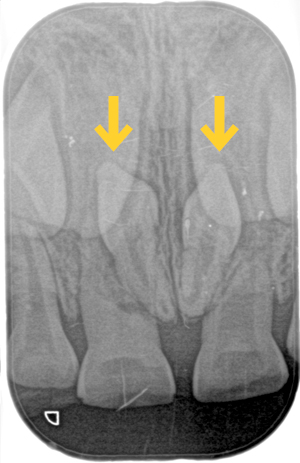

過剰歯がありました

健診に来てくれた子の前歯のレントゲンを撮影したところ

「過剰歯」がみつかりました。

向きが逆向きで2本あり生えてきそうにありません。

今後乳歯や永久歯への影響を注意深く確認していきます。